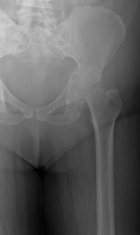

63 year old female with history of breast cancer

Zoom image: Radiological image Radiological image.